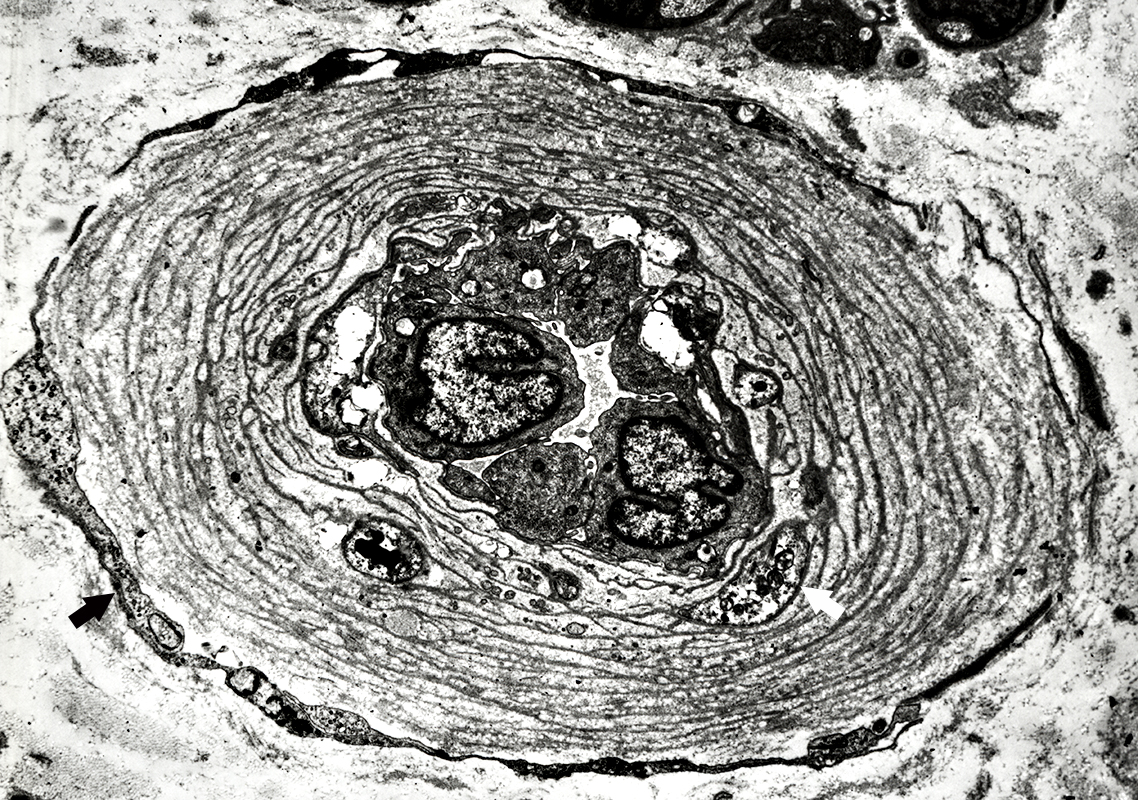

Muscle (Endomysial) Capillaries: Ultrastructure

From: R Schmidt

|

Endomysial Capillaries: Normal

Lumen: Patent

Endothelial cell processes

Form inner layers of capillary wall

Cytoplasm often contains small vesicles

Outer Wall: Surrounds endothelial cells & their processes

Pericyte processess (White arrow)

Basal lamina (Black arrow)

Mostly Single layer

Thicker than muscle basal lamina (Right & Bottom Right)